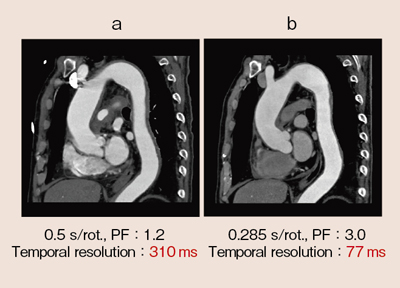

胸部CT検査は,心臓の拍動の影響が大きいが,Dual Source CTの特徴であるFlash Spiralを使うことで,ほとんど輪郭のぼやけない画像を得ることができる。ただし,すべてに適用することが良いというわけではない。例えば,大動脈疾患が疑われるような患者に対しては推奨値で撮影すると,図10aのような画像になる場合が多い。しかし,Flash Spiralを大動脈の精査に使うことで,心電非同期でも77msの時間分解能で,図10bのような画像を得ることができる。また,フォローアップにおいて造影剤の低減ができることからも,Flash Spiralは有用であると言える。

![]() 図10 胸部大動脈CTA |